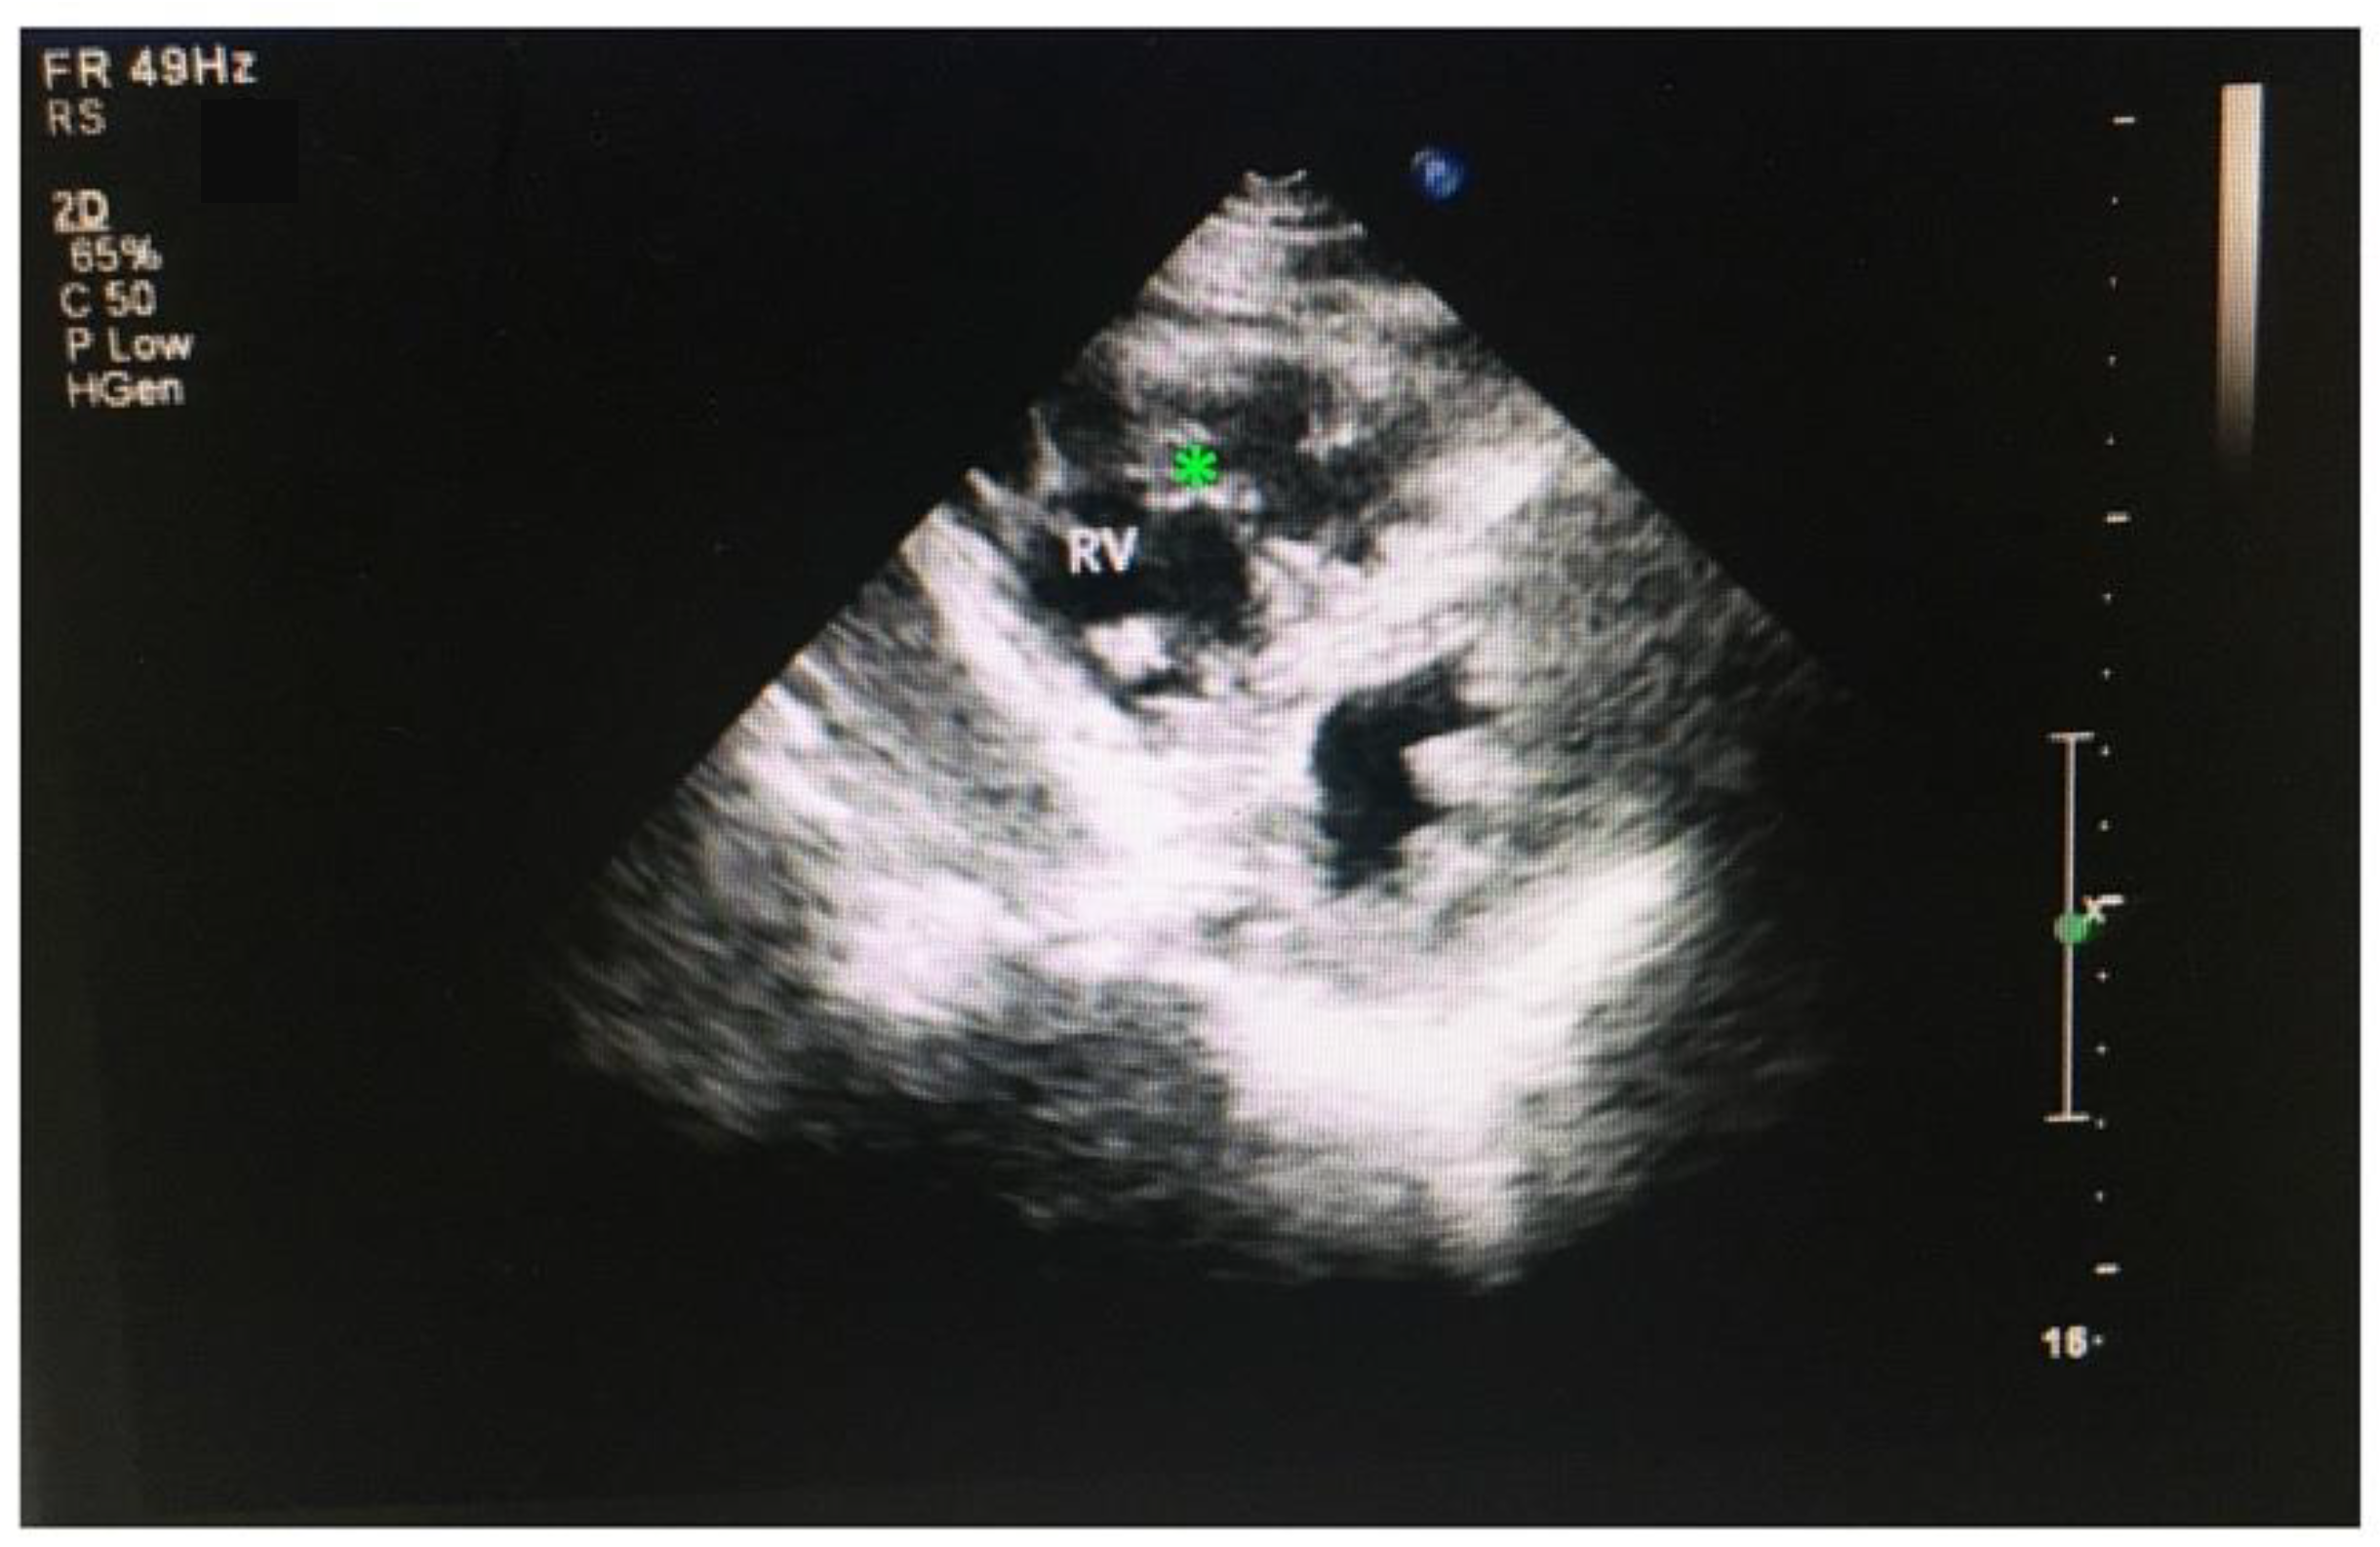

3.5. RVNC Does Not Associate with Reduced Contractility